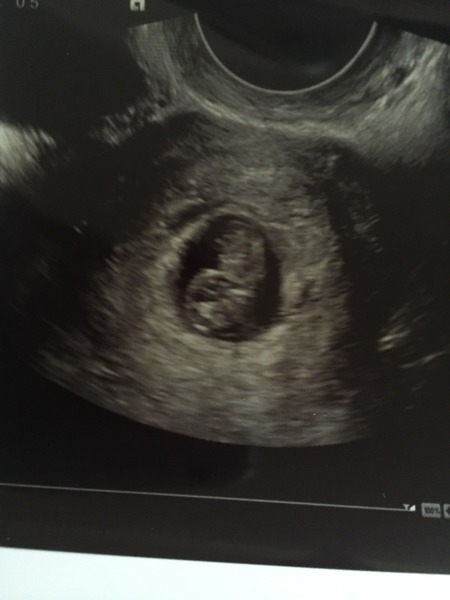

northern so sorry to hear your struggling with anxiety as well getting through the first trimester after having experienced a loss is so hard. Even after 12 weeks your still anxious as you feel no movements and your symptoms start to fade until we start feeling the kicks our minds will never be put to rest. Really hoping they can help you get to the bottom of the cysts. If there not causing you any problems I am sure they won't effect you Hun it's very common I had one on my right overy before I fell pregnant and I conceived on my right side there prob seen it since but nothing has ever been noted. How many do they think you have? Can see baby in you picture it's so lovely to see baby your be surprise how much baby grows over the next few weeks. I couldn't believe my 6 week scan then my 9 week scan the difference. hope you get answers to out your mind at rest soon hun.

Back in 3 weeks for a rescan again - we'll see what's happened to them by then. Plus side is got to see baby again :) much clearer as its an internal scan.

Lovely scan northern Flowers sorry they couldn't be more helpful with the cysts! Hope ur ok. X

So sorry they couldn't help anymore northern it defiantly does not look like a molar pregnancy so I really wouldn't worry about that. They love to scare us don't they these doctors then send us away for 2-3 weeks thinking we can wake up singing every morning. As for clots it's away from baby it's a mystery Hun I can understand why you have anxiety I think any of us would if we was going through what your going through. Have they taken any blood work from you? On a postive note Hun you have a healthy baby there growing away it's a very clear picture. Hand holding with you these next few weeks Hun wishing the days away. Big hugs I'm sure everything will be fine it's just the Unknown.

Hi Keys, no they didn't do any blood work today but have said they will do when I go back if they still don't know what's happening. I've googled ultrasounds of molar pregnancies today and I don't think t looks like that either (today's scan you can't see the circles / cysts they are on about, but could see on the one i put on yesterday). Going away next week which I'm quite pleased about as means it's something to keep my mind busy on something else for a bit!